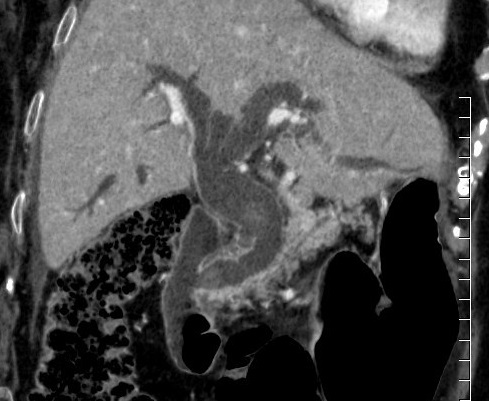

Image radiologique d'une CSP en

coupe TDM axiale avec de conrtrast

intraveineuse . Aspect de dilatation et

stricture stenosant systematise des voies

biliaires intrahepatique . Foie

elargir et splenomegalie |

Image de dialtation des voies

biliaires intrahepatique . Foie est elargir

et rude , veine porte dilate ,

splenomegalie , n' a pas de calcul biliaire

. Cholangite sclerosant primitive du foie en

coupe frontale ( TDM plus C+ ) |